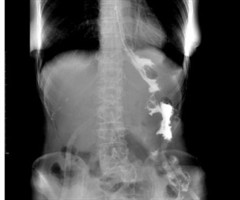

胃癌合并胃间质瘤和空肠瘤样钙盐沉积症1例

关键词:胃癌;胃肠间质瘤;空肠;瘤样钙盐沉积症 中图分类号:R656.6+1文献标志码:B 文章编号:2097-7174(2025)10-0980-02 DOI:10.3969/j.issn.2097-7174. 2025.10.010 胃...